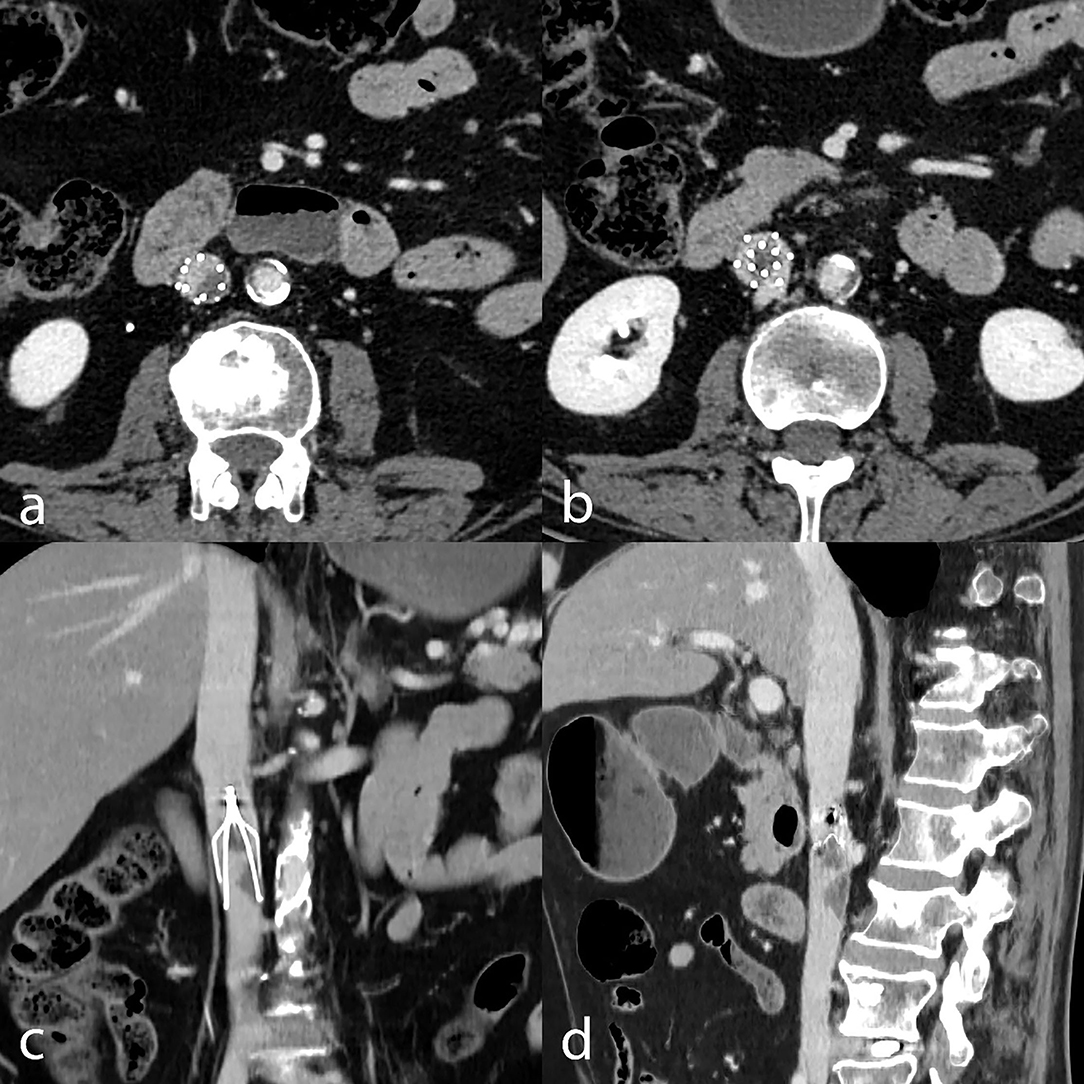

Technical irretrievability is considered in the presence of a large thrombus in the filter (>30% of filter volume, Figure 1) or deep transmural penetration. Although not considered a criterion of irretrievability, filter tilt is associated with increased technical unsuccessfulness (45).

Figure 1. Technical irretrievability due to thrombus inside the filter. CT venography with axial (a,b), coronally reformatted (c), and sagittally reformatted minimum-intensity projection (d) images show thrombotic material stuck in the filter, precluding retrieval.